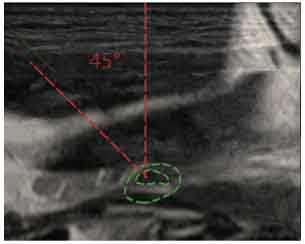

CT-Ultrasound Fusion in PCNL

CT-Ultrasound real-time fusion

3D navigation and tracking